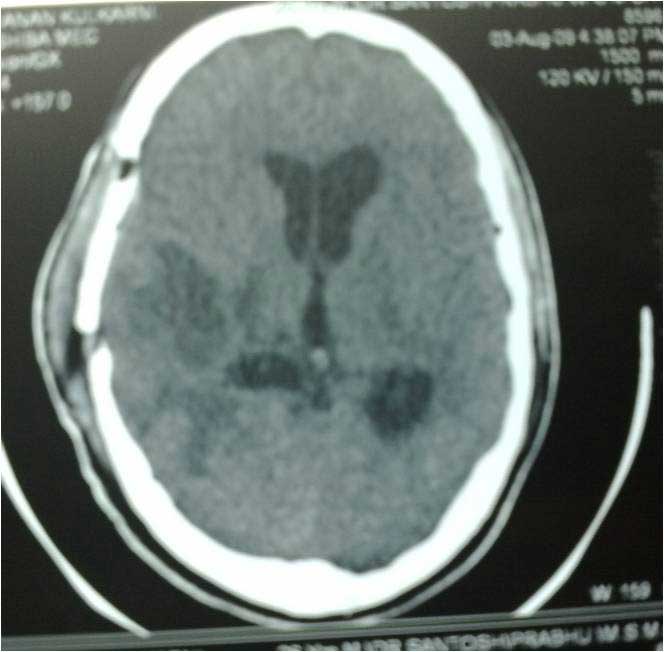

Brain Abscess Brain Abscess Post OP 2 Clinical Intra OP ,After Excising The Granuloma Intaop Scalp Abscess CT Scalp Abscess Cerebellar Abscess Post OP Clinical Cerebellar Abscess Brain TB Granuloma Post OP CT Scan Brain Infection Brain Abscess Preop MRI 2 Brain Abscess PRE OP Clinical 1 Brain Abscess PRE OP Brain Abscess Intraop 2 Brain Abscess Following Shunt Temporal Abscess T2W of TB Granuloma Scalp Abscess Preop CT Marking PRW OP MRI of TB Granuloma Post OP Clinical Photo Post OP Cerebellar Abscess Post OP Brain Abscess Intraop Specimen of Granuloma